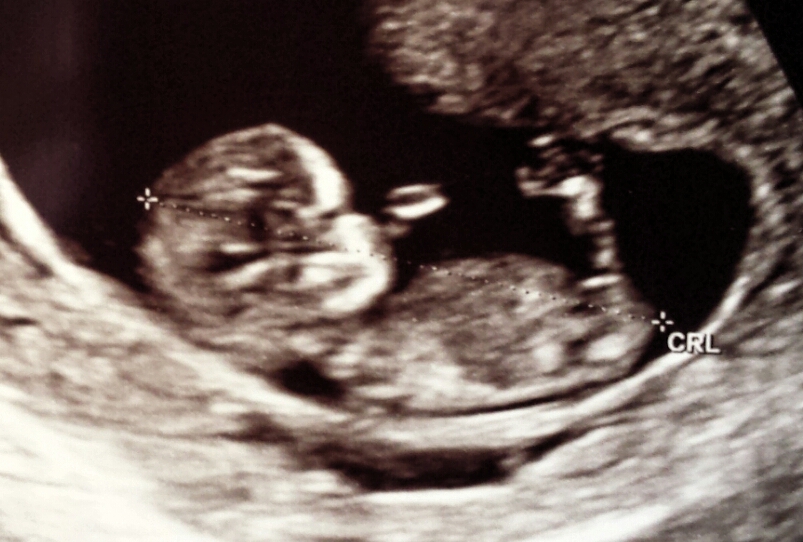

Can't see second pic. But based on the first, I'd guess girly. Still early though and not a super clear shot.

Girly but early :)

Girl:)